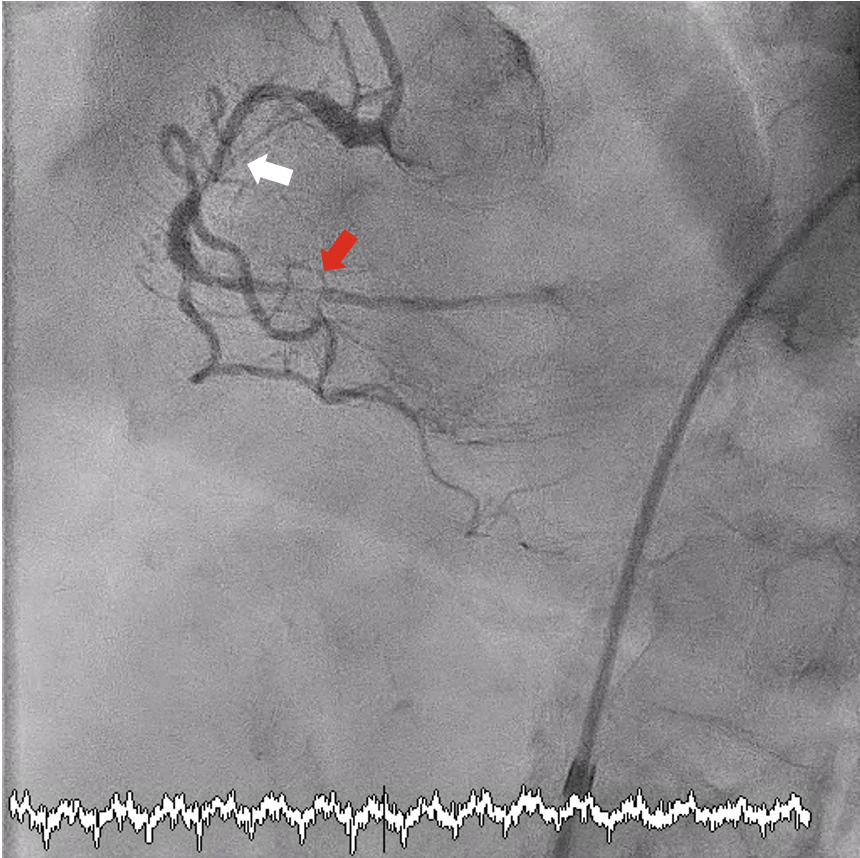

Excimer laser coronary atherectomy (ELCA; 0.9-mm catheter, escalated to 80 mJ/mm²/80 Hz, 25 cycles) (Philips) was used to facilitate crossing. During ELCA, hypotension (85/50 mm Hg) and chest pain occurred, which were attributed to dissection with slow flow (Figure 2, Video 1). Sequential balloon dilatations restored flow and hemodynamics stabilized at approximately 120/80 mm Hg without inotropes. Intravascular ultrasound (IVUS)-guided treatment included a 2.0 × 30-mm SeQuent Please NEO drug-coated balloon (B. Braun) distally and 2 overlapping Coroflex ISAR NEO drug-eluting stents (B. Braun) (2.25 × 38 mm and 3.5 × 32 mm) proximally, with excellent final angiographic (Figure 3, Video 2) and IVUS results.